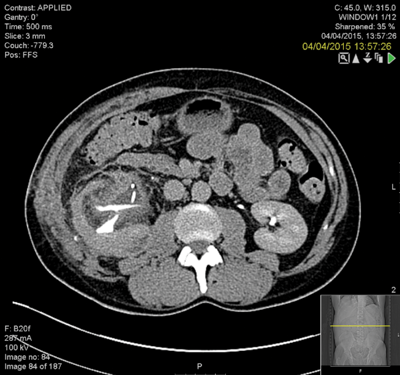

The kidney was grossly inflamed and it was very difficult to identify the anatomy. The surgeon considered a nephrectomy but persevered to complete the repair. The patient remained in hospital for two weeks postoperatively with low grade pyrexia and a CT revealed a clot in the collecting system and possible calyceal perforation (Figure 4) and extravasation. This was seen to have improved on a subsequent CT (Figure 5).

Figure 5.

The stent was removed at three months and a retrograde examination in theatre and live fluoroscopy revealed good drainage.